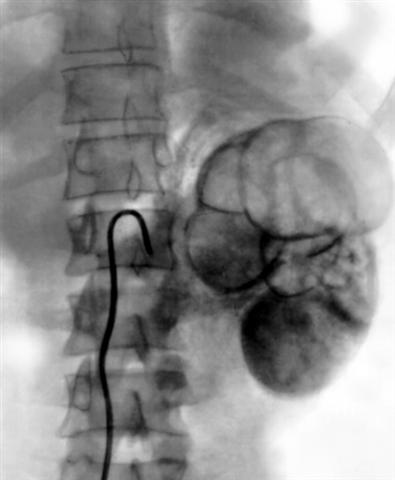

Рис. 9б. Сегментарная ангиограмма левой почки при фиброзно-кавернозном туберкулезе левой почки и туберкулезе левого мочеточника: в верхнем сегменте левой почки отсутствует васкуляризация, определяются множественные тонкостенные полости, в нижнем сегменте васкуляризация снижена, имеется несколько полостей. |